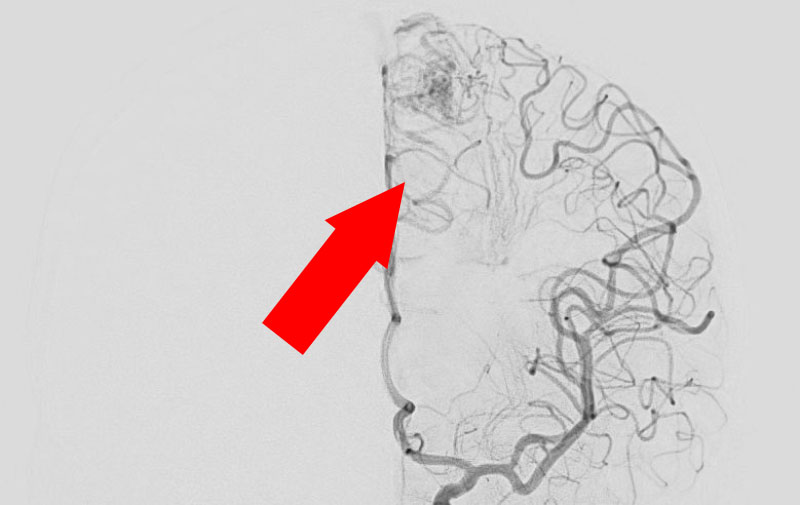

No.1585 手術前